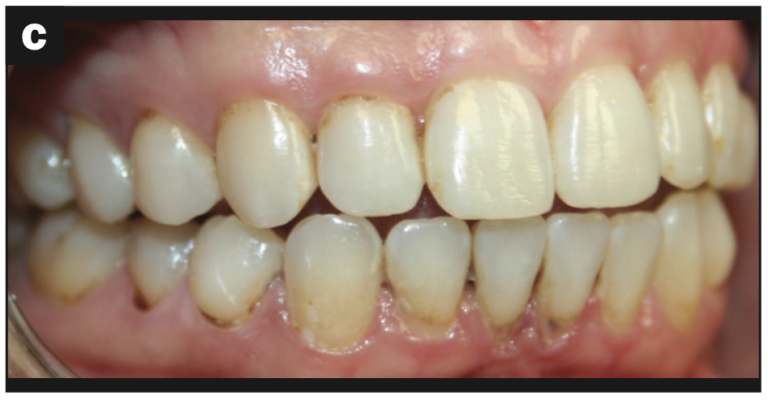

Intraoral images were captured, focusing on three surfaces of each tooth: buccal, occlusal/incisal, and lingual surfaces. The following issues were identified:

- Abfraction with decay (Figures 2a and 2b)

- Abfraction lesions (Figures 2c and 2d)